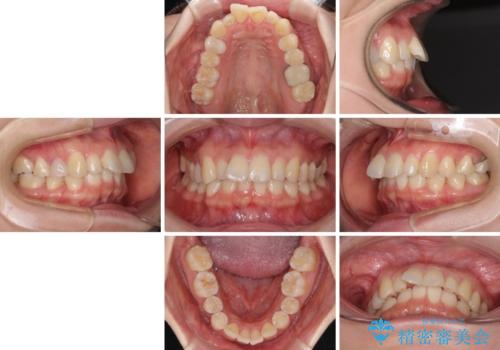

先天欠損のある歯列 インビザライン矯正

- 上顎前歯の突出感を気にして来院された患者様です。

下顎前歯2本が先天欠損しており、上顎歯列に対して、下顎歯列がアンバランスに小さい状況でした。

左右上顎側切歯2本が矮小歯であるため、上顎の抜歯ではなく、IPR(歯と歯の間を削る)と歯列全体の後方移動によってバランスを整えることとしました。

目立ちにくい装置を希望されたため、インビザラインにて治療を行うこととしました。

歯列のバランスが悪く、インビザライン矯正特有の奥歯の噛みにくさがなかなか改善されず、治療期間が長期化してしまいました。